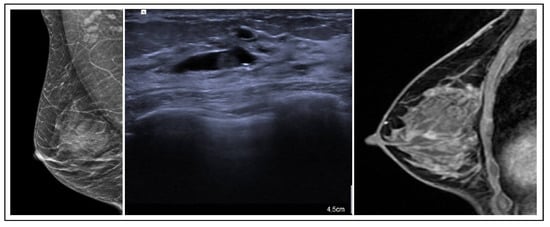

RSs usually appear on mammography as a spiculate lesion or a region of structural distortion with a radiolucent core, sometimes accompanied by calcifications. Tomosynthesis aids in identifying RSs on mammograms [19]. The appearance can vary on ultrasound, ranging from no distinct correlation to a hypoechoic irregular mass. Moreover, MRI findings may exhibit variability and lack specificity. RSs may present without any MRI correlation, displaying no enhancement, or manifest as mass lesions with irregular margins or non-mass enhancement [20]. These imaging characteristics require caution, as RSs can resemble invasive breast cancer (Figure 3). Histologically, central fibroelastosis is surrounded by compressed glandular structures and cysts, sometimes associated with benign or malignant changes [21].

Figure 3. RS radiological features.